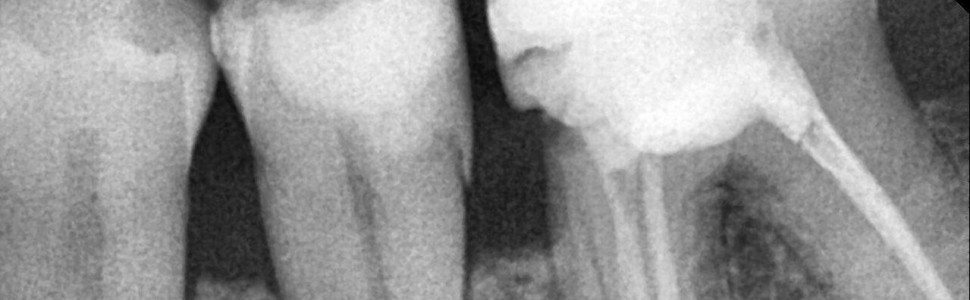

Zgłosił się do mnie pacjent, którego skierowano do specjalisty periodontologa w celu konsultacji i leczenia ubytków kostnych w okolicy zębów 34-36. Pacjent jest ogólnie zdrowy. W trakcie wywiadu ogólnostomatologicznego zgłaszał dyskomfort oraz krwawienie dziąseł podczas szczotkowania zębów, utrzymujące się od wielu miesięcy. Na zdjęciu RTG celowanym dostarczonym przez pacjenta stwierdziłam ubytki nadkostne w okolicy 34-36. Jakie działania powinnam podjąć?

W przypadku, gdy pacjent osiągnął prawidłową higienę jamy ustnej (FMPS<20%), ale utrzymuje się stan zapalny (BOP+), a PD ≥5,5 mm, można rozważyć leczenie chirurgiczne. Obecność ubytku nadkostnego skłania do wyboru minimalnie inwazyjnego zabiegu oczyszczenia po podniesieniu płata (open flap debridement – OFD). Zabieg taki pozwala na eliminację zapalenia i spłycenie kieszonek patologicznych, ale może też generować recesję dziąsła. Dlatego wykonanie OFD w odcinku przednim jest przeciwwskazane. Widoczne na RTG nadkostne ubytki w okolicy 34-36 nie dają możliwości odtworzenia tkanek przyzębia, a więc są przeciwwskazaniem do periodontologicznych zabiegów regeneracyjnych.

Ryc. 1. Nadkostne ubytki w okolicy 34-36.